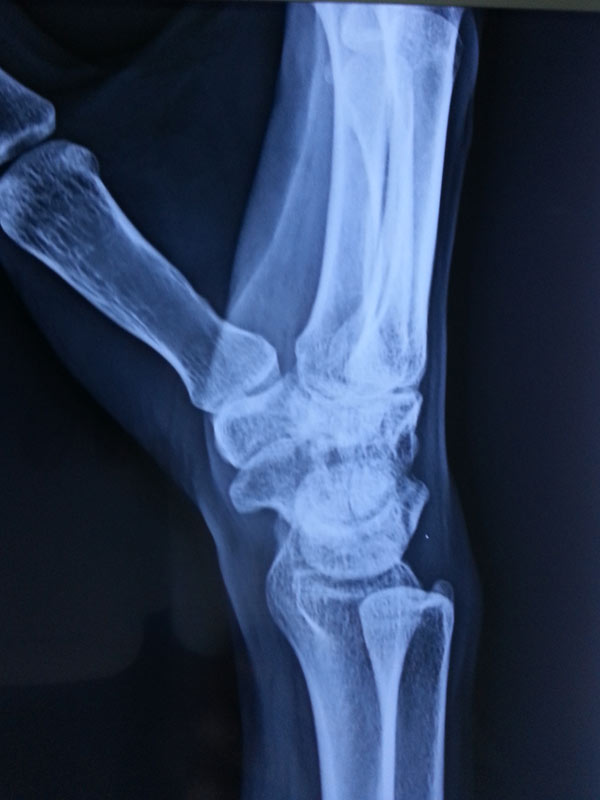

A case of scaphoid non-union

The young, male patient had the fracture of Rt scaphoid/ due to falling on an outstretched hand. The scaphoid fracture was treated, with the plaster cast for 1 ½ month elsewhere. Fracture of Rt Scaphoid was not united. This condition is called, the scaphoid non-union. It was treated with open reduction, and the iliac crest, bone grafting, and K wire stabilization.

Before Surgery